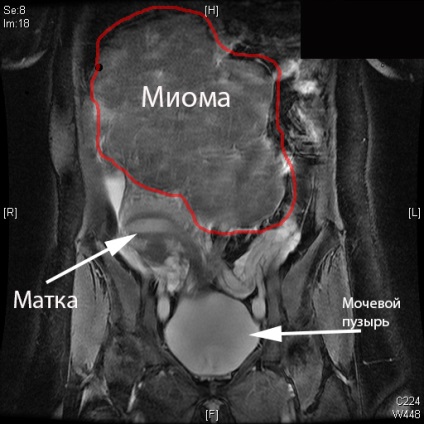

RMN-ul a imaginii abdomenului

histeromyomele

tumori frecvente Mioma- ale uterului, in special din grupa de vârstă de 30-35 de ani.

Educația este structura musculo-conjunctiv, în curs de dezvoltare din miometru. Nodurile pot avea dimensiuni diferite și raportul dintre mușchi și țesut conjunctiv, de multe ori sunt multiple.

Poate fi localizat: subseros (creșterea podbryushinnye este direcționată departe de stratul miometrul la stratul mucos) sub membrana mucoasă (creștere intră în uter), interstițial - varianta cea mai comuna (creștere se produce în interiorul stratului muscular).

RMN-ul este o valoare de diagnostic in perioada preoperatorie cu interventii chirurgicale conservare a sânului. Este de asemenea posibil tomografia exploatație, în scopul de a clarifica diagnosticul cu date incorecte cu ultrasunete. utilizat în mod avantajos tomogram ponderat T1 pe care fibrom este definită ca formarea unei contururi netede clare, cu o intensitate a semnalului moderat scăzută. Când procesul de lungă durată, apariția unor focare de necroză și calcificare în interiorul tumorii. In tomogram, se pare ca formarea de mare intensitate neuniformă în structură, cu bordura o intensitate mai mică.